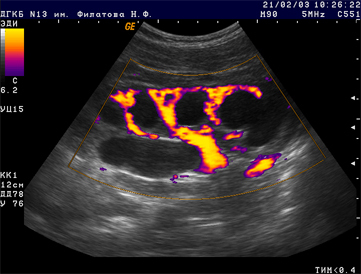

1. Обследование детей начинается с ультразвукового исследования почек и мочевыводящих путей. Исследования выполняются высококвалифицированными специалистами на современной аппаратуре.

В настоящее время наиболее информативными методами выявления обструкции пиелоуретрального сегмента считают ультразвуковое исследование, экскреторную урографию и радиоизотопное исследование. УЗИ прекрасный метод скринингового обследования, при котором выявляется расширение лоханки и чашечек у детей любого возраста, в том числе и у новорожденных. У младенцев первых месяцев жизни необходимо проводить дифференциальный диагноз гидронефроза с пиелоэктазией или функциональным расширением ЧЛС, которое исчезает самостоятельно в течении 3-6 мес.

УЗИ с лазиксной нагрузкой позволяет уточнить данный диагноз. Перед исследованием проводится водная нагрузка (вв капельное введение глюкозы 5% из расчета 15млкг веса за 30 мин до исследования). Детей старшего возраста просят опорожнить мочевой пузырь. Грудному ребенку устанавливают уретральный катетер на весь период исследования, чтобы исключить ложноположительный результат, обусловленный переполненным мочевым пузырем. Измеряется поперечный максимальный размер лоханки и чашечек в стандартном положении. Далее вводят лазикс вв из расчета 0,5-1.0мг/кг. Затем измеряют размеры лоханки и чашечек через 10,20,40,60,120 минут после введения лазикса.

Признаками органической обструкции считают:

- Длительное ( более 60 минут) расширение ЧЛС на (более чем 30% ) от исходного размера на фоне лазикса и адекватной гидратации при сохраненном почечном кровотоке.

- Появление болевого синдрома, тошноты и рвоты свидетельствует в пользу обструкции.

- Уменьшение скорости почечного кровотока и повышение на 15% индекса сопротивления на фоне лазиксной нагрузки.